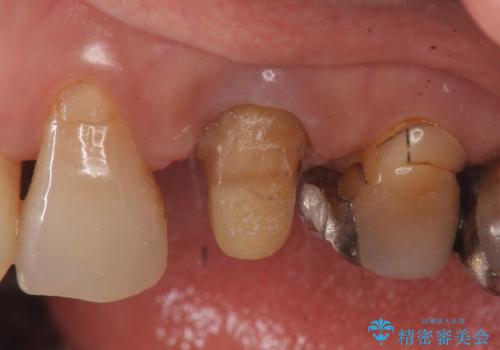

- 他院にて左上3番の被せ物を勧められたが、根管治療からやり直したいと当院にいらっしゃった方の症例です。

再根管治療後、オールセラミッククラウンによる補綴を行いました。